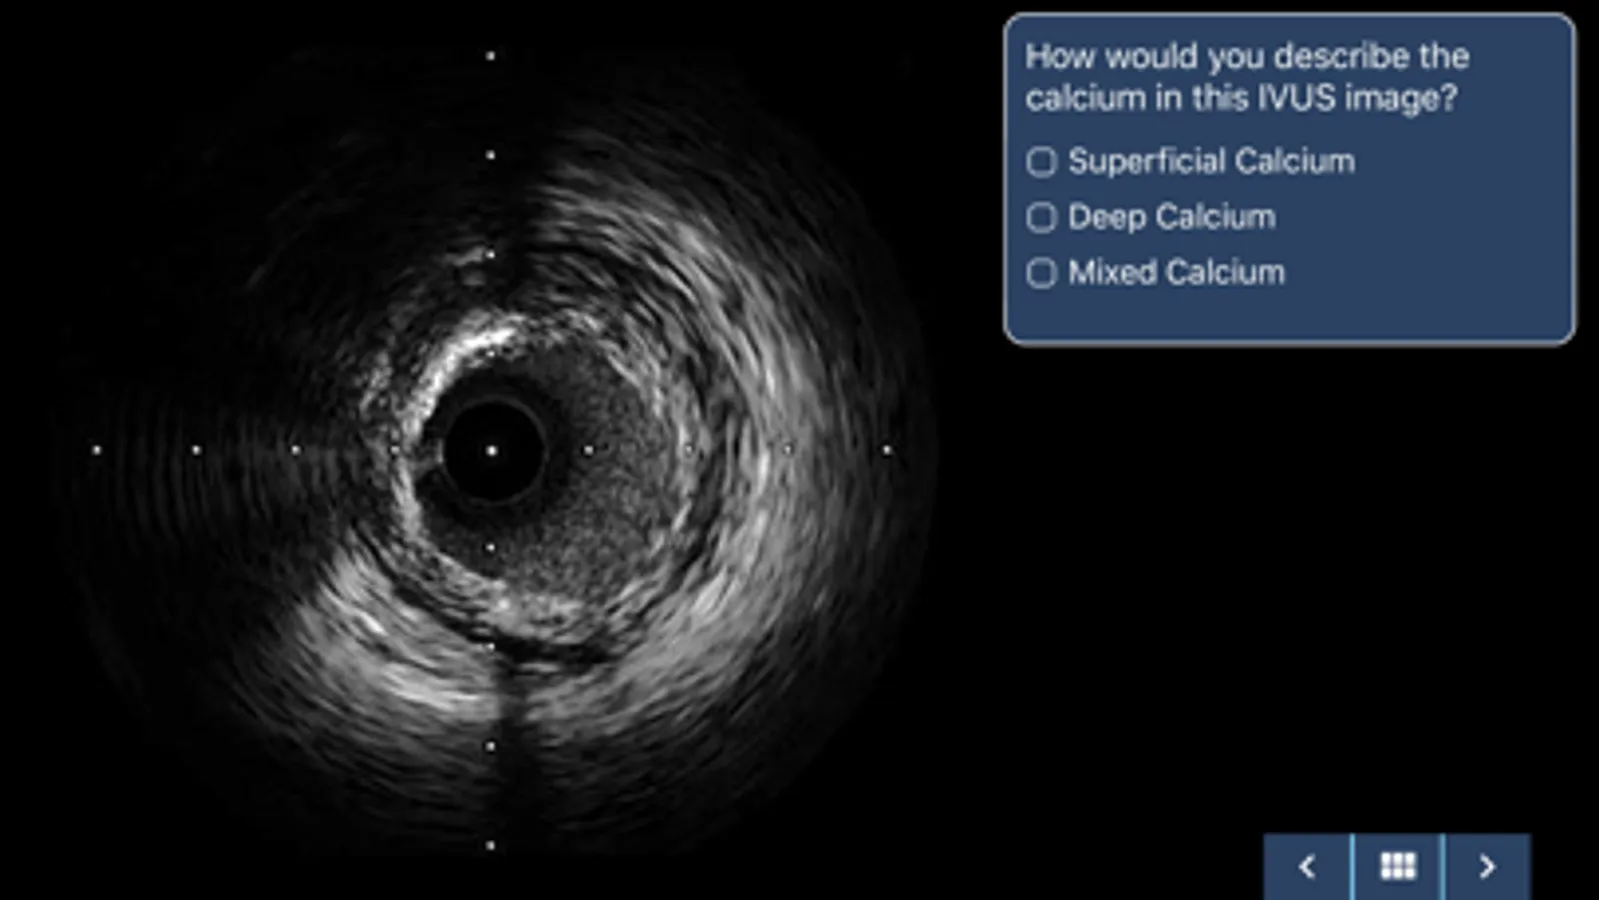

• IVUS image and FFR waveform interpretation guide with questions

• Practice IVUS measurements and compare results with real case examples